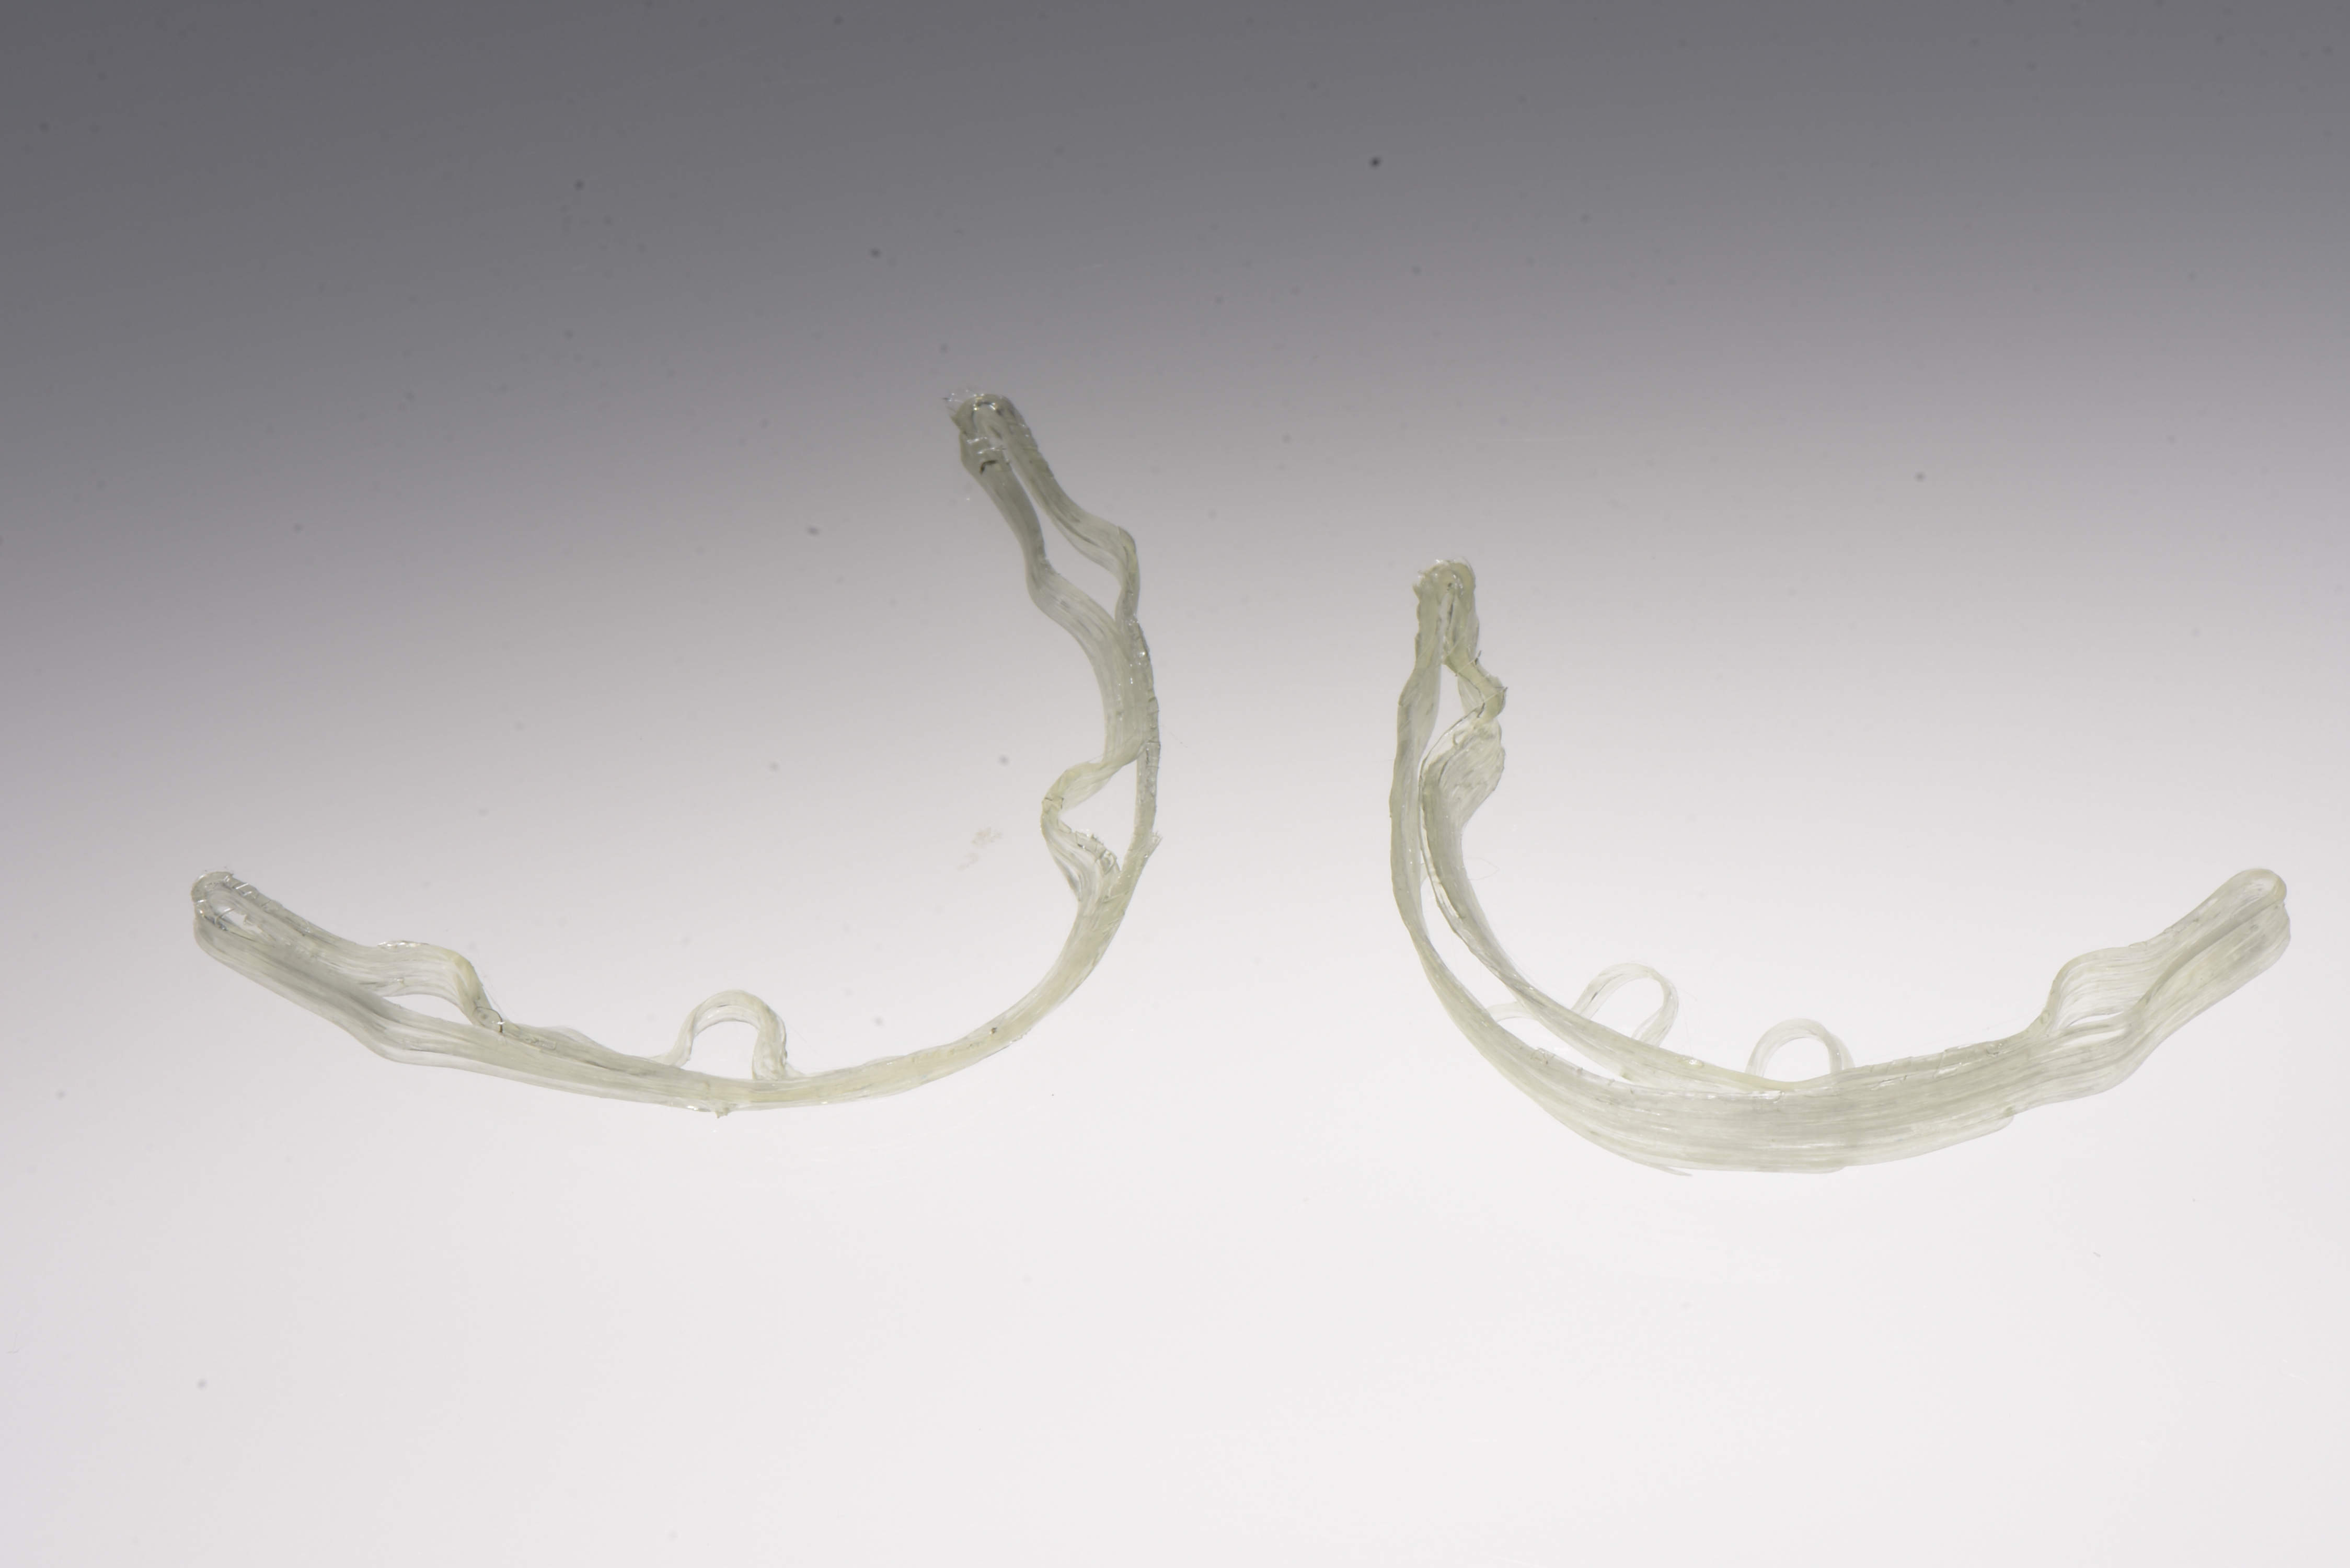

Nell’ultimo incontro prima della finalizzazione delle protesi si verifica la passività ed il corretto accoppiamento protesico di barre in CrCo laser melting sulla base delle quali successivamente sono realizzate le barre in fibra di vetro continuo stampata in 3D. (fig.16-21)

Le protesi definitive su barra in fibra di vetro stampata in 3D sono consegnate nell’ultimo appuntamento. Le viti di ritenzione sono serrate a 25ncm come da indicazione del produttore e i fori passanti sono chiusi con PTFE e composito. L’occlusione viene ricontrollata con carta di articolazione e i ritocchi sono eseguiti come ultima fase di consegna. Alla paziente sono fornite le prime istruzioni di igiene orale domiciliare. (fig. 22-28)

foto 22 produzione barra in fibra di vetro continuo stampata in 3d

foto 23a consolidamento rinforzo in fibra di vetro continuo stampata in 3d a link implantari

foto 23b fasi di lavorazione e stratifica materiale